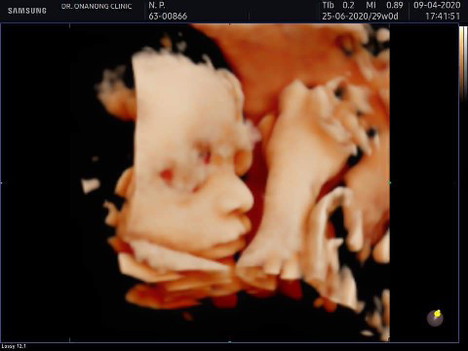

มีใครรอคลอดแต่ยังไม่มีอาการที่จนะคลอดบ้างคะ กำหนดคลอด25มิ.ย จะอยู่ที่40w+3d อาการยังนิ่งอยู่เลย ใจจดใจจ่อ อยากเห็นหน้าตัวเล็กแล้วคะ